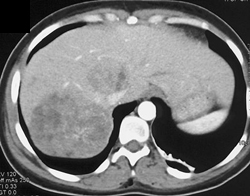

Metastases in A Fatty Liver